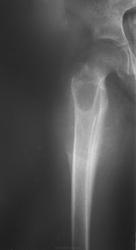

Девочка 9 лет. Родители отмечают, что 2 месяца назад девочка начала предъявлять жалобы на боли в правой пятке. Обследовались, патологии в стопе не нашли. Ребёнок постепенно начал хромать. А несколько дней назад обнаружили припухлость в в/3 бедра. Болей в бедре нет, как ночных, так и дневных. Температура не повышалась. Обратились за помощью - выполнены рентгенограммы, затем - КТ.

Злокачественная опухоль - виден луковичный периостит, инвазивный рост с лизисом кости. Но какая? Вроде бы растет из костного канала. Остеосаркома? Юинг? для этих опухолей структура какая-то больно хрящевая, мягкотканная. Хондросаркома? В таком возрасте? Почему нет клиники злокачественной опухоли кости, прежде всего - болей?

Согласна. Только периостит не луковичный, четкий лизис с козырьками Кодмена-явный признак злокачественности. А насчет болей, действительно в жизни всякое бывает, но, думаю, что ребенок не может отличить их от болей в пятке (!), а прихрамывание может быть и следствием щажения конечности.

Коллеги, давайте правильно применять термины. Периостит - окончание воспаления, применяется при остеомиелите. При опухоли - периостоз - окончание избытка, продуктивного процесса. Здесь есть "козырек Кодмена", спикулообразный периостоз, но есть так же луковичный (слоистый) периостоз, который хорошо виден на отдельных КТ-срезах. Другое дело, что для диф. диагноза опухоли (то что процесс агрессивный - сомнений не вызывыает) это, по большому счету, ничего не дает. Однако, обратите внимание на вздутие. Считаю возможны варианты телеангиоэктатической или гигантоклеточной остеосаркомы. Так же не считаю возможным исключить саркому Юинга.

Да, рентгенкартина неоднозначна, конечно, в первую очередь надо исключать зло (Юинга, остеогенную), но не уверена на 100%, что это они, спикул нет, есть луковичный периостит ниже основного очага, но это не критерий злокачественности, вздутие. Был бы возраст помладше, в первую очередь подумала бы о гистиоцитозе или туберкулезе. Еще мысли об аневризмальной кисте и ГКО. Очень хочется узнать результаты гистологии.